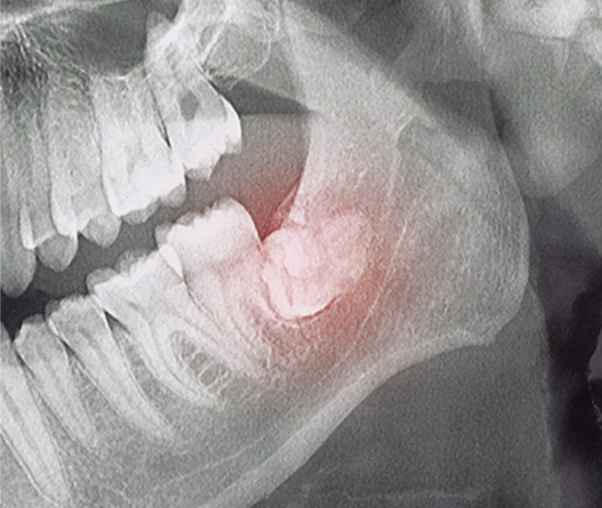

철저한 신경손상 가능성 분석

사랑니의 뿌리는 신경과 가까운 경우가 많아, 발치 전 신경 손상 가능성에 대해 철저히 분석한 뒤 손상이 없도록 정밀한 치료를 진행해야 합니다.

신경과 턱뼈의 손상 우려

뼈 속에서 사랑니가 자라는 경우 종양발생의 위험이 있으며, 신경과 턱뼈의 손상을이 일어날 수 있어 부작용에 더욱 주의해야 합니다.

사랑니 근처에는 신경이 있어요!

사랑니 뿌리근처에는 아래턱 신경이라는 커다란 신경이 지나갑니다. 개인마다 다르지만 뽑는 과정에서 신경에 손상을 일으킬 가능성이 있습니다. 신경손상 가능성에 대한 사전 분석이 필요하며 손상 가능성이 있다고 판단되는 경우 경험 많은 의사에게 조심스러운 발치 및 후 처리가 요구됩니다.